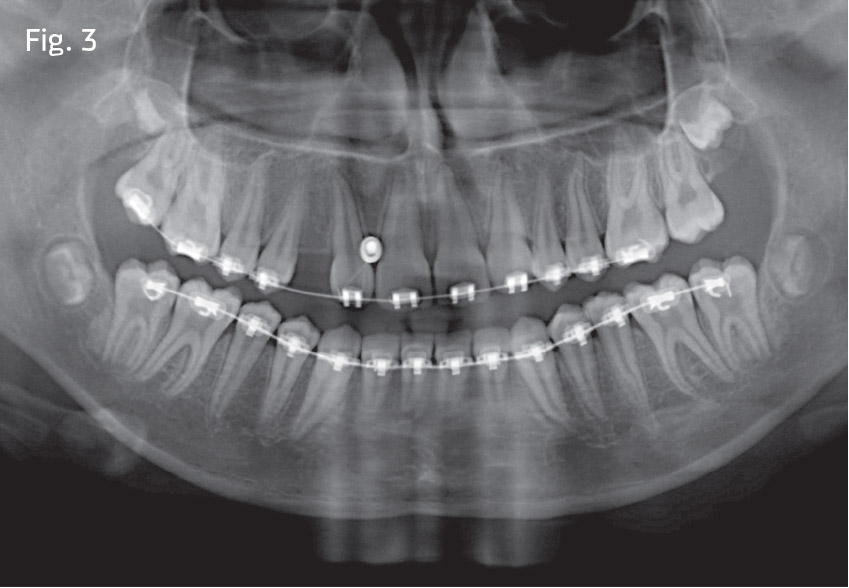

Approximately seven months into treatment, we placed the TAD mesial to the upper right lateral incisor position (Fig. 3) and used indirect anchorage to protract the right buccal segment. Sliding mechanics were used in conjunction with Class III elastics on the right—again, trying to maintain as much anterior torque as possible.